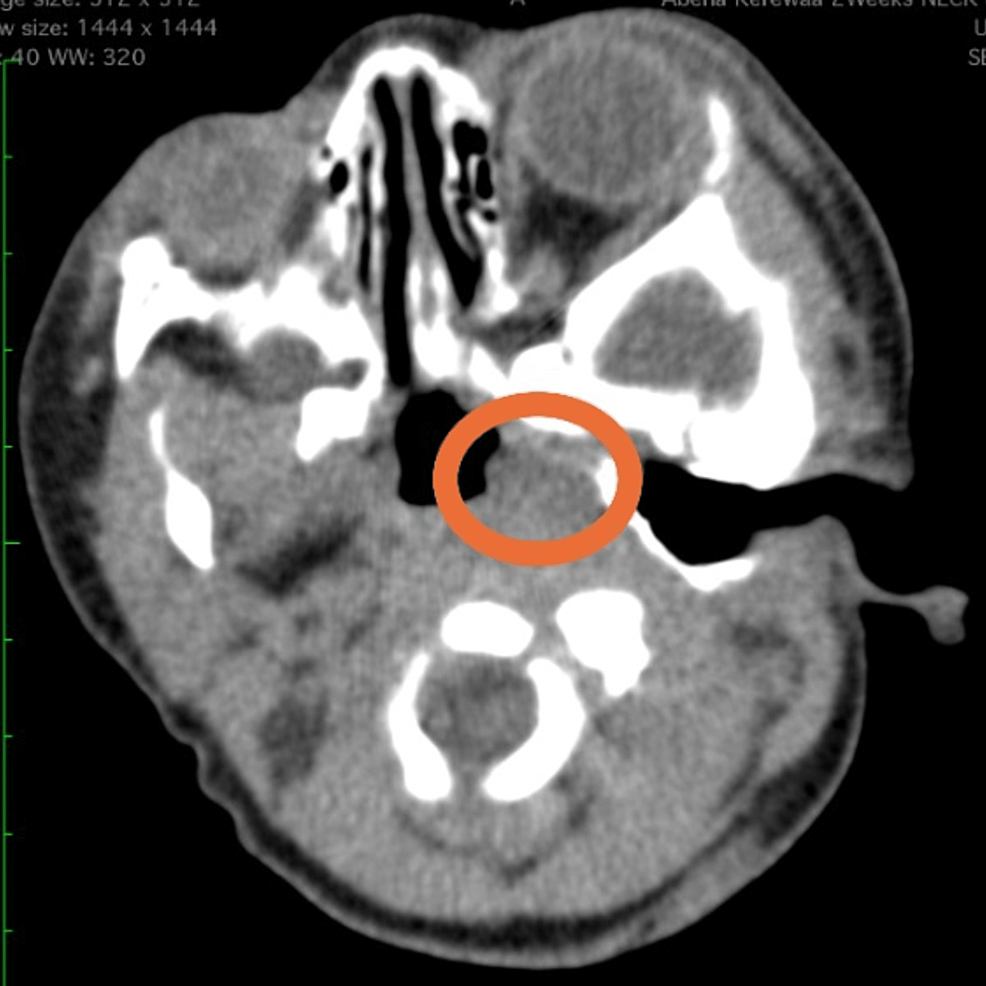

Figure 3 from Unusual Presentation of Laryngeal Cavernous Hemangioma Hemangioma Larynx hemangiomas of the larynx or trachea are often seen in children who have multiple hemangiomas appearing in a particular. laryngeal hemangiomas exhibit a spectrum of manifestations, ranging from asymptomatic lesions to those causing severe airway. It is rare in the. laryngeal hemangioma management requires personalized approaches informed by diverse therapies, clinical expertise, and. adult laryngeal hemangiomas. Hemangioma Larynx.